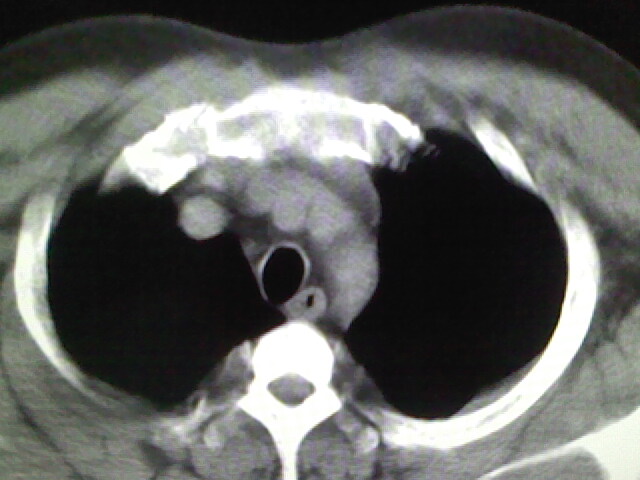

标题: CT17932:临床怀疑肺栓塞

男,34岁,自觉右侧胸痹,胸闷3天余

左上肺局限片状透光度增强区,肺纹理稀少,可考虑局限性肺气肿。

右侧肺动脉似见密度稍低影,请在机器的薄层上再看看有没有充盈缺损。

左上肺局限性肺透光度减低,肺纹理稀少;这虽然符合早期肺栓塞的改变,但与局限性肺气肿难以鉴别。

书上讲早期肺栓塞就是表现肺透光度减低,肺纹稀少。